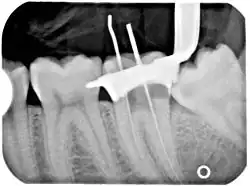

Another common complication of root canal therapy is when the entire length of the root canal is not completely cleaned out and filled (obturated) with root canal filling material (usually gutta percha). On the other hand, the root canal filling material may be extruded from the apex leading to other complications. The X-ray in the right margin shows two adjacent teeth that had received bad root canal therapy. The root canal filling material (3, 4, and 10) does not extend to the end of the tooth roots (5, 6 and 11). The dark circles at the bottom of the tooth roots (7 and 8) indicated infection in the surrounding bone. Recommended treatment is either to redo the root canal therapy or extract the tooth and place dental implants. Poor quality filling material or sealant may also cause root canal treatment to fail.[48]